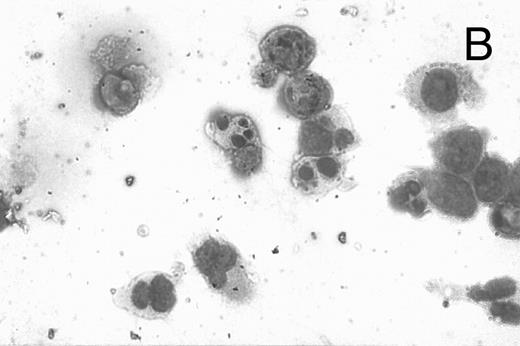

A number of antagonists and promoters of apoptosis have recently been described. The bcl-2 family, which now consists of 7 different proteins encoded by 7 different genes, has now been characterized (Vaux and Strasser37 and the references contained within). Bcl-2 and bcl-XL are expressed in numerous cell types and are potent antagonists of apoptosis. We were unable to detect bcl-XL expression in HL-60R or HL-60 cells as has previously been described,43 but found that bcl-2 is highly expressed in these cells and is also cleaved during CD437-mediated apoptosis (Fig 6). Phosphorylation of bcl-2 has been previously described as a mechanism for bcl-2 inactivation during the apoptotic process.44 Whether cleavage of bcl-2 represents another mechanism by which bcl-2 is inactivated remains to be determined. That this cleavage of PARP, CPP32, and bcl-2 does not simply represent random cleavage of a number of proteins is suggested by our inability to detect cleavage of lamin B (data not shown), which is often found cleaved in a variety of forms of programmed cell death.39 41 CD437 also markedly inhibited growth of the K562 cells (Fig 1C) but contrary to HL-60R cells apoptosis was not noted until 144 hours of exposure to CD437, as indicated by internucleosomal degradation demonstrated by gel electrophoresis (Fig 7). We also examined the ability of CD437 to induce PARP cleavage and apoptosis in primary leukemic blasts obtained from a patient with acute myelogenous leukemia. As shown in Fig 8C, enhanced PARP cleavage was noted within 24 hours after exposure to 1 μmol/L CD437, with the apoptotic morphology noted at 48 hours of exposure (Fig 8A and B).

CD437-mediated apoptosis in primary leukemia cells. Leukemic blasts were isolated as described in the Materials and Methods. Cells were exposed to 1 μmol/L CD437 for various periods of time and PARP cleavage was assessed as previously described. (A) Leukemic cells exposed only to vehicle for 48 hours. (B) Leukemic cells exposed to 1 μmol/L CD437 for 48 hours. (C) CD437-mediated PARP cleavage. Lanes 1 and 3, cells exposed to vehicle only for 24 and 48 hours, respectively. Lanes 2 and 4, cells exposed to 1 μmol/L CD437 for 24 and 48 hours, respectively.